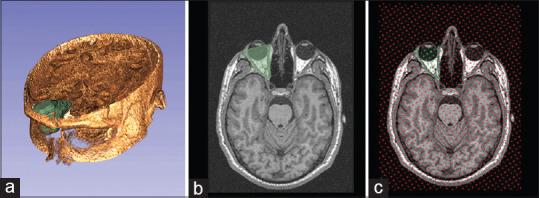

Current volume measurement techniques, for the orbit, are time-consuming and involve complex assessments, which prevents their routine clinical use. In this study, we evaluate the applicability and efficacy of stereology and planimetry in orbital volume measurements using magnetic resonance imaging (MRI).

Prospective imaging study using MRI. Sheep craniums and human subjects were evaluated. Water-filling measurements were performed in animal skulls, as the standard validation technique. Planimetry and stereology techniques were used in each dataset. Intraobserver and interobserver reliability testing were applied.

In stereology customization, 1/6 systematic sampling scheme was determined as optimal with acceptable coefficient of error (3.09%) and low measurement time (1.2 min). In sheep craniums, the mean volume measured by water displacement, planimetry, and stereology was 17.81 ± 0.59 cm, 18.53 ± 0.24 cm, and 19.19 ± 0.17 cm, respectively. Planimetric and stereological methods were highly correlated ( = 0.94; ≈ 0.001). The mean difference of the orbital volume using planimetry and stereology was 0.316 ± 0.168 cm. In human subjects, using stereology, the mean orbital volume was found to be 19.62 ± 0.2 cm with a CE of 3.91 ± 0.15%.

The optimized stereological method was found superior to manual planimetry in terms of user effort and time spent. Stereology sampling of 1/6 was successfully applied in human subjects and showed strong correlation with manual planimetry. However, optimized stereological method tended to overestimate the orbital volume by about 1 cc, a considerable limitation to be taken in clinical practice.